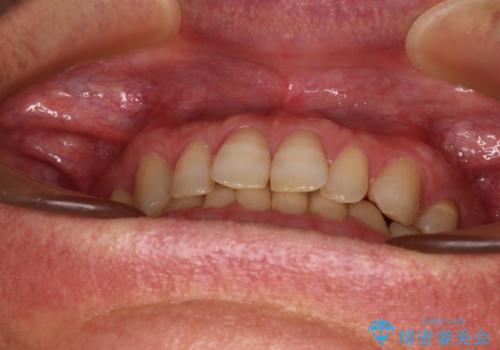

- 前歯のデコボコと隙間の空いた歯列を気にして来院された患者様です。

下顎前歯が隠れるほどのディープバイトにより、強い咬合力と突き上げで上顎歯列に隙間が空いている状態でした。